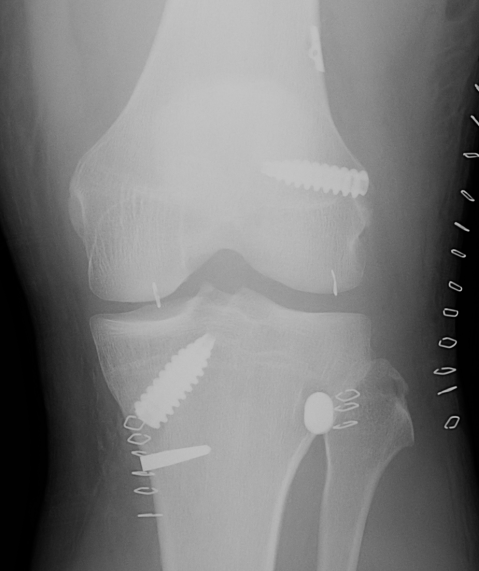

ACL + LaPrade reconstruction of LCL and popliteus